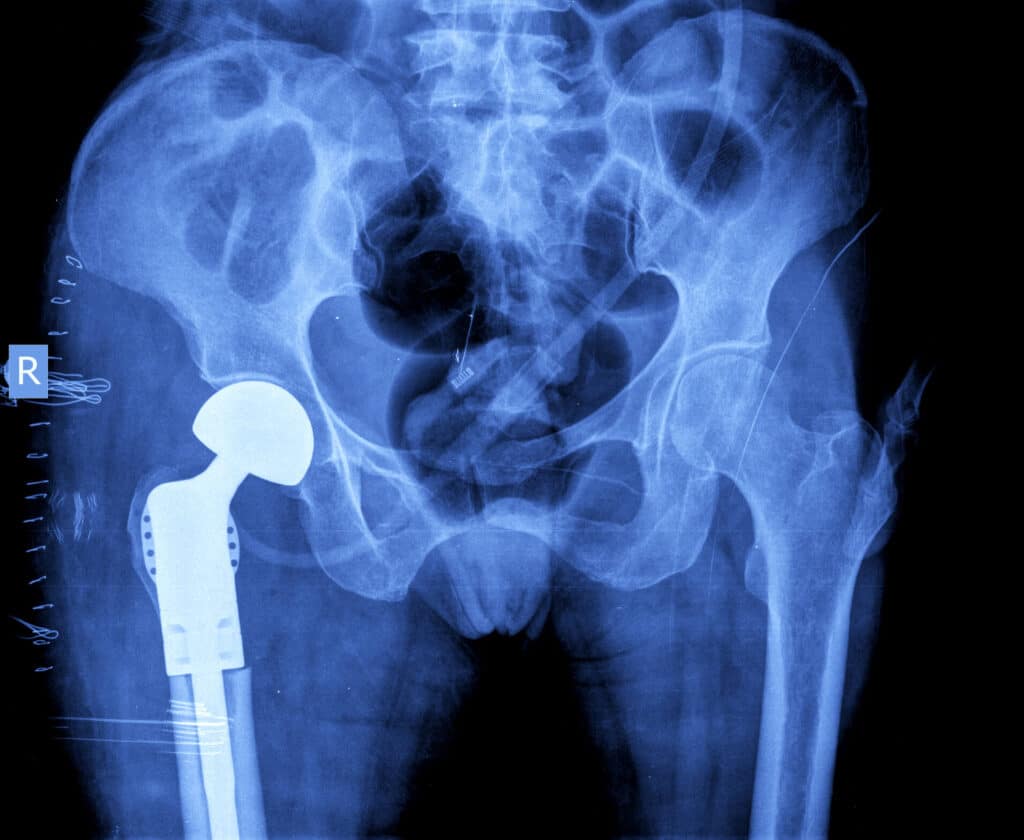

The reason I needed hip-replacement surgery in the first place was that a congenital flaw in my left hip’s joint socket and cartilage deteriorating in the socket of my right hip were making it harder and harder for me to be active. Hiking is one of my favorite forms of recreation, so I was happy to learn that hip-replacement surgery could make it possible for me to keep enjoying it.

Because both sides of my hips had problems, I needed two separate hip-replacement surgeries. The first was in 2005 on my right hip. The second was in 2007 on my left hip. Each surgery involved removing unhealthy natural body parts and replacing them with factory-made pieces – ceramic on the right side, metal on the right.

I was advised that I could expect these implants to last for decades. However, only a couple of years after the second surgery, the metal hip-replacement on my left side went bad. It happened while I was out hiking. I was going up a steep trail when, all of a sudden, I started feeling intense pain.

I found out about the design problems a few days later when I went to see my orthopedic surgeon to have this hiking injury treated. My doctor showed me a letter he had received from the hip-replacement joint maker, stating that the company had ordered a market recall of the devices due to safety and health concerns.

After I signed up with Weitz & Luxenberg, they sent a letter to my doctor to give him instructions about what to save from the defective implant he would soon be removing and what to send to the lab for testing afterward, such as tissue samples. That they knew this would be helpful to my case was impressive.

The money was important because I ended up staying in the hospital two separate times for operations to remove the defective implant in my left hip and replace it with a reliable and safe one.